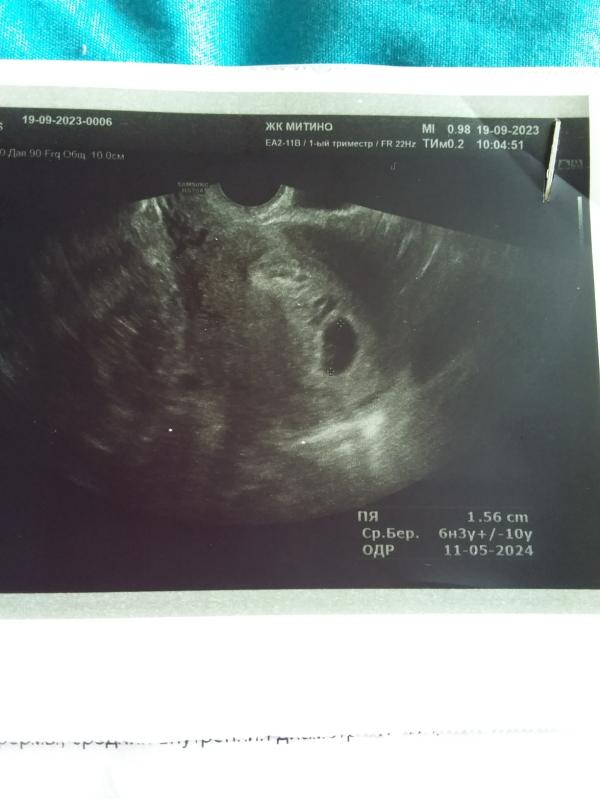

Сегодня сделала УЗИ. Плачу до сих пор 😭 срок беременности 7нед и 4дня, по УЗИ 6 и 3. Но эмбриончик еще не сформирован. И УЗИст (старый дед), сказал что возможно замершая или неправильный срок..... У меня уже была замершая, боюсь вторую я не переживу 😭😭

У вас там вроде желточный мешочек есть- это хорошо. Подождите пока, может срок действительно неправильный.

Может эмбриона ещё не видно, но желточный мешочек уже видно хорошо, переделайте обязательно. Все у вас хорошо 🌷💕

У меня тоже 6 недель, в субботу увидели только плодное яйцо.